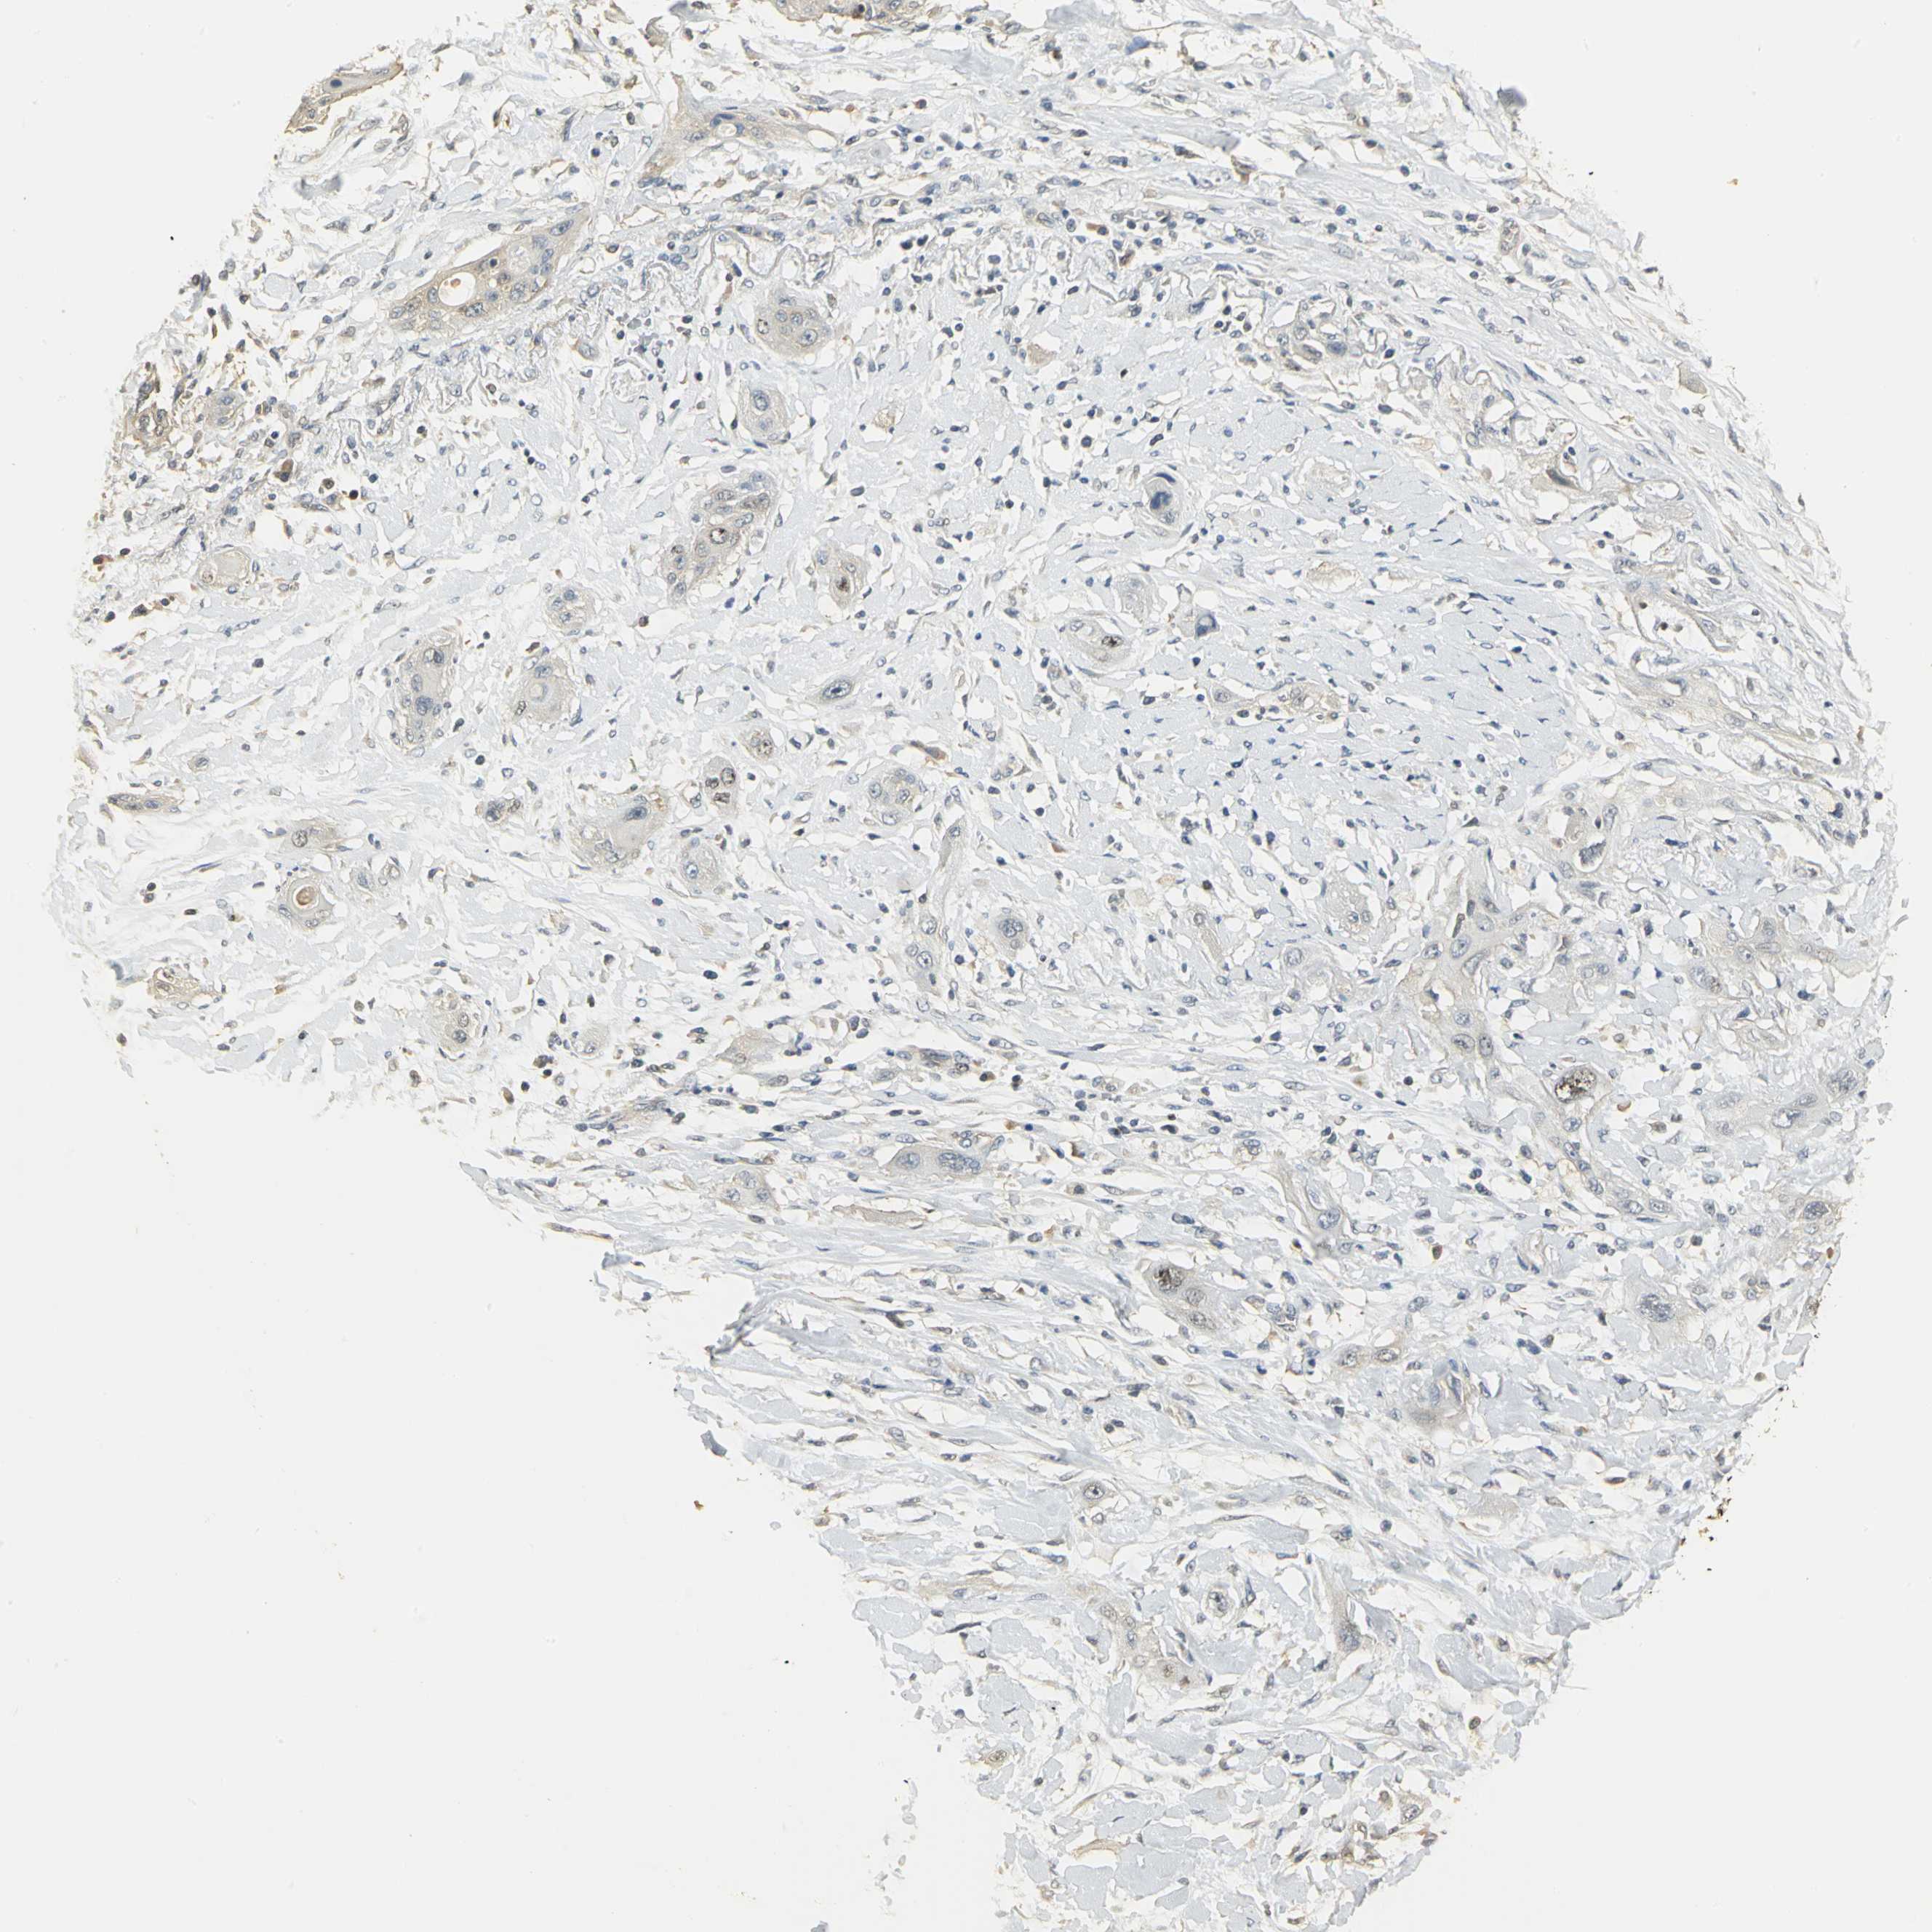

CANCER LUNG CANCER Show tissue menu

Lung cancer

Human cancer